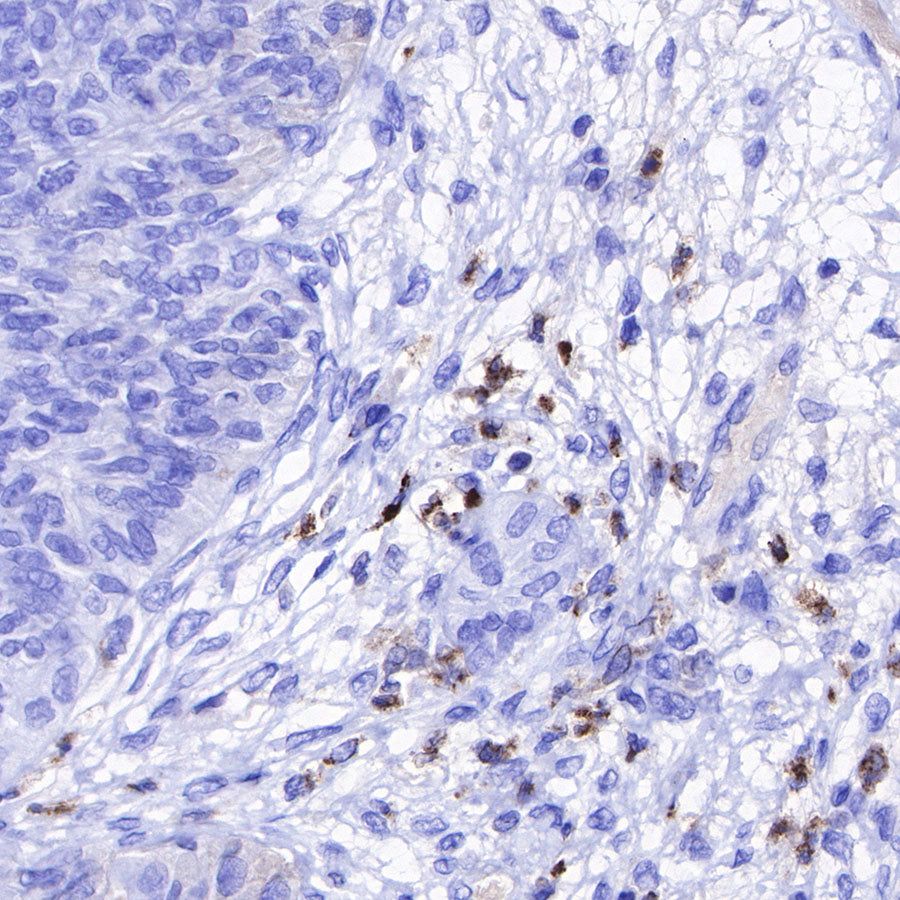

Immunohistochemistry

IHC shows positive staining in paraffin-embedded human lung squamous cell carcinoma. Anti-Lysozyme antibody was used at 1/100 dilution, followed by a HRP Polymer for Mouse & Rabbit IgG (ready to use). Counterstained with hematoxylin. Heat mediated antigen retrieval with Tris/EDTA buffer pH9.0 was performed before commencing with IHC staining protocol.

IHC shows positive staining in paraffin-embedded human endometrial carcinoma. Anti-Lysozyme antibody was used at 1/100 dilution, followed by a HRP Polymer for Mouse & Rabbit IgG (ready to use). Counterstained with hematoxylin. Heat mediated antigen retrieval with Tris/EDTA buffer pH9.0 was performed before commencing with IHC staining protocol.